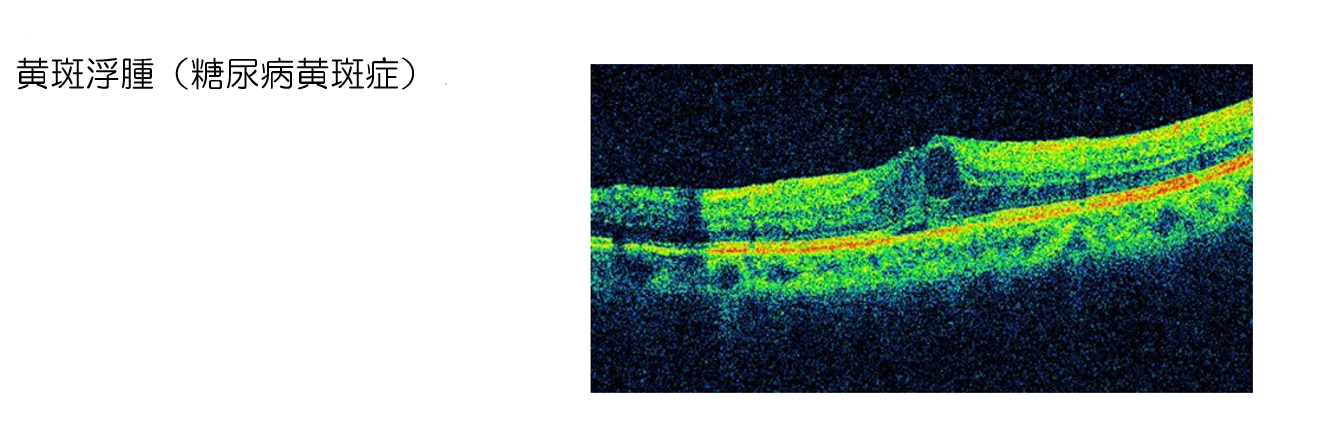

糖尿病網膜症治療

最近生活習慣の変化により糖尿病が増加しています。糖尿病で大切なことは、その合併症である腎臓(透析)・神経(壊疽)・眼(失明)を予防することです。これから糖尿病と目についてのお話しをします。糖尿病白内障・新生血管緑内障・眼筋麻痺・角膜上皮障害など多くの症状がありますが、特に糖尿病網膜症が大切です。糖尿病網膜症は成人の失明原因のトップとなっているのです。

眼にはカメラのフィルムにあたる網膜という場所があります。網膜・腎臓は血管が豊富な場所です。糖尿病とは基本的に血管がつまる病気です。したがって、糖尿病が続く(糖尿病の罹患期間が長い)と網膜がいたんで(糖尿病網膜症が進行して)きます。

糖尿病網膜症と時期・症状・所見

フルオレセイン造影剤を静脈注射した後、眼底の網膜血管の写真を撮影する検査です。糖尿病をはじめ眼底疾患を理解する上で大きな役割を果たします。螢光造影は、網膜の毛細血管レベルの形態変化や血管壁の機能障害など、検眼鏡では観察できない病態を解明します。網膜全体の血管閉塞の程度や新生血管の発生部位を知る上で重要です。これにより光凝固の適応や糖尿病網膜症の時期を判定します。